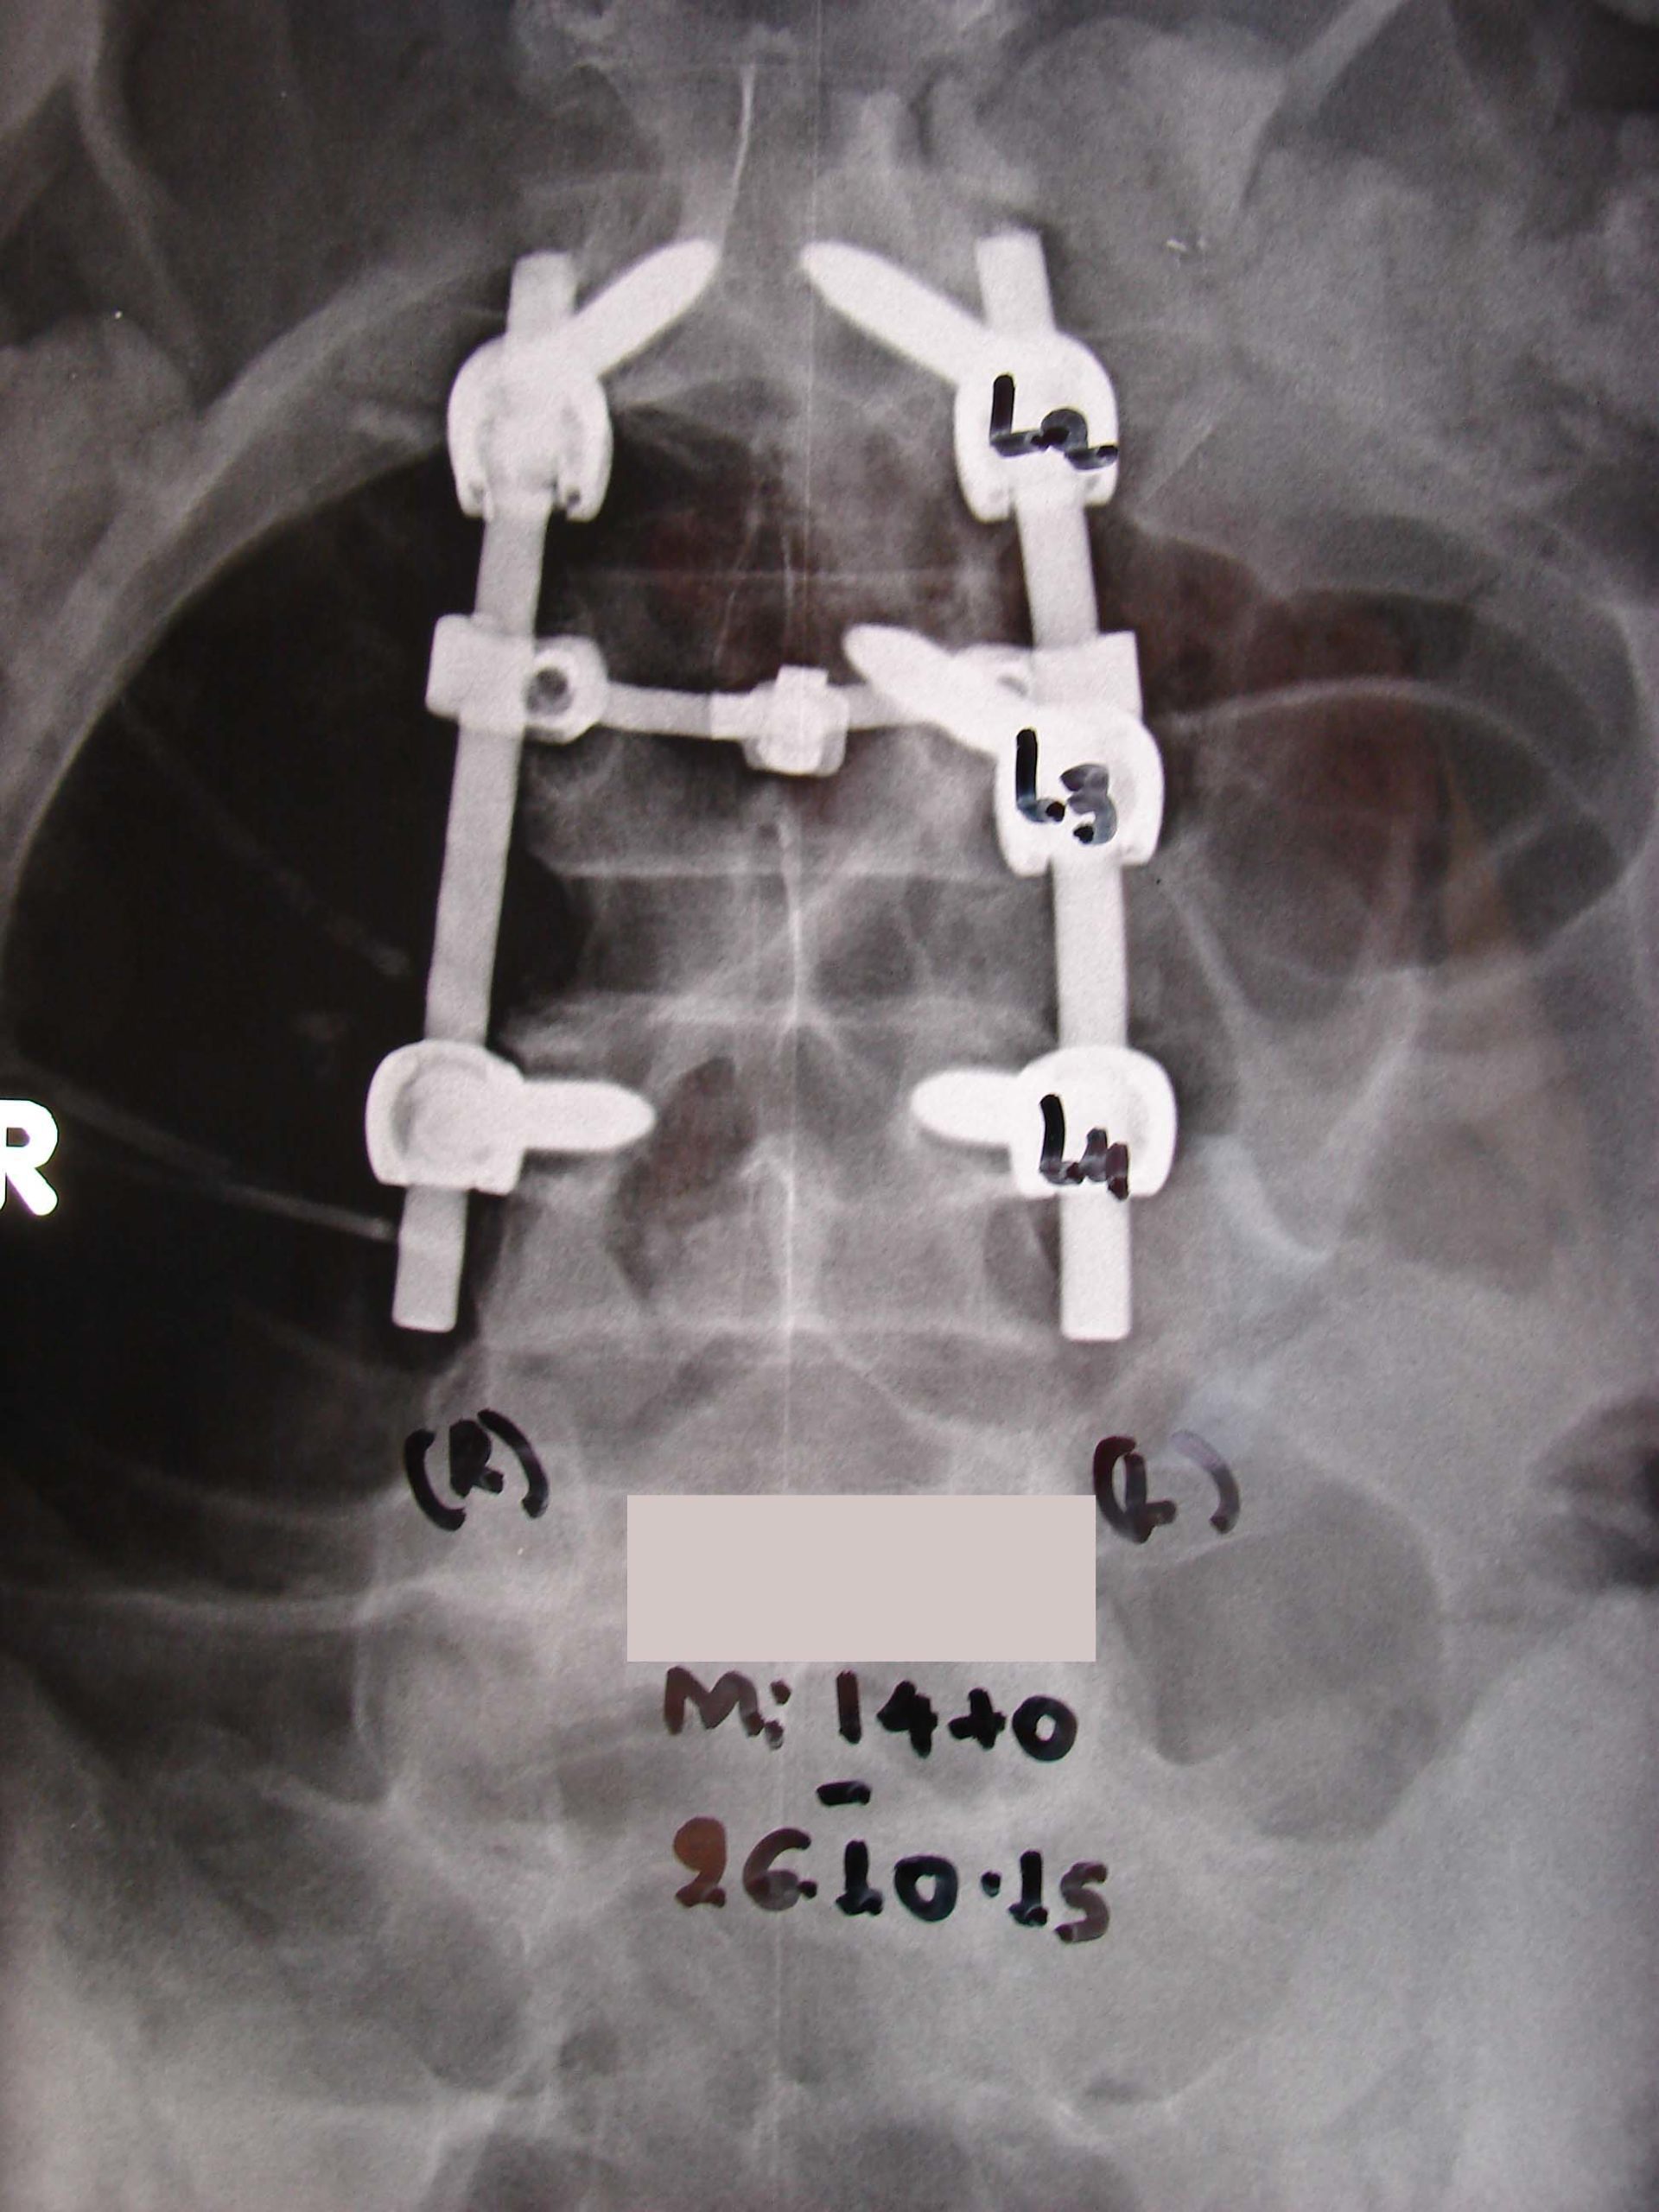

Εικόνα 5 Διεγχειρητική προσθιοπισθία ακτινογραφία, μετά την τοποθέτηση των βιδών. Στον 3ο οσφυϊκό σπόνδυλο δεξιά, δεν έχει μπει βίδα.

Εικόνα 6 α, β Πρώτες μετεγχειρητικές, προσθιοπισθία (α) και πλαγία (β), ακτινογραφίες.

Μετά την αφαίρεση του οστεοειδούς οστεώματος και τη διαταραχή της ακεραιότητας της σπονδυλικής Δεξιάς διάρθρωσης Ο2-Ο3, έχει σταθεροποιηθεί η περιοχή Ο2-Ο3-Ο4 με σταθερό σύστημα σπονδυλοδεσίας δια διαυχενικών βιδών και ράβδων. Δεν έχει τοποθετηθεί βίδα στον 3ο αυχενικό σπόνδυλο δεξιά, λόγω της επέμβασης σε μεγάλη έκταση στο δεξιό μίσχο (pedicle), που ενδεχομένως θα περιόριζε σημαντικά την δημιουργία συμπαγούς οστού, μετά την τοποθέτηση του αλλομοσχεύματος.